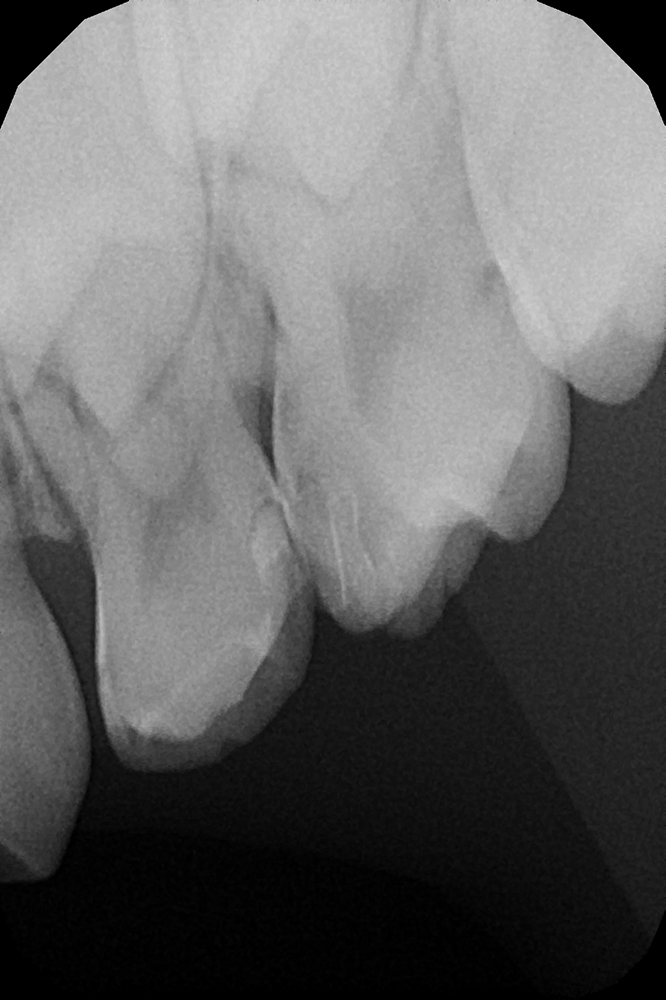

Диагностика и лечение скрытого кариеса на постоянном зубе у семилетнего ребёнка